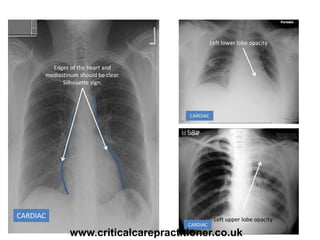

CARDIAC

Edges of the heart and

mediastinum should be clear.

Silhouette sign.

Right middle lobe opacity

Right upper lobe opacity

Left lower lobe opacity

Left upper lobe opacity

• #30 The heart (a soft tissue density structure - near white) lies adjacent to lung tissue (near air density - near black). A crisp contour or 'silhouette' is formed at the interface of these two tissue densities. Loss of clarity of the right heart contour (formed by the right atrium) implies disease of the right middle lobe which lies next to the right atrium. Loss of distinction of the left heart contour indicates an abnormality of the lingula (part of the left upper lobe which wraps over the left ventricle).